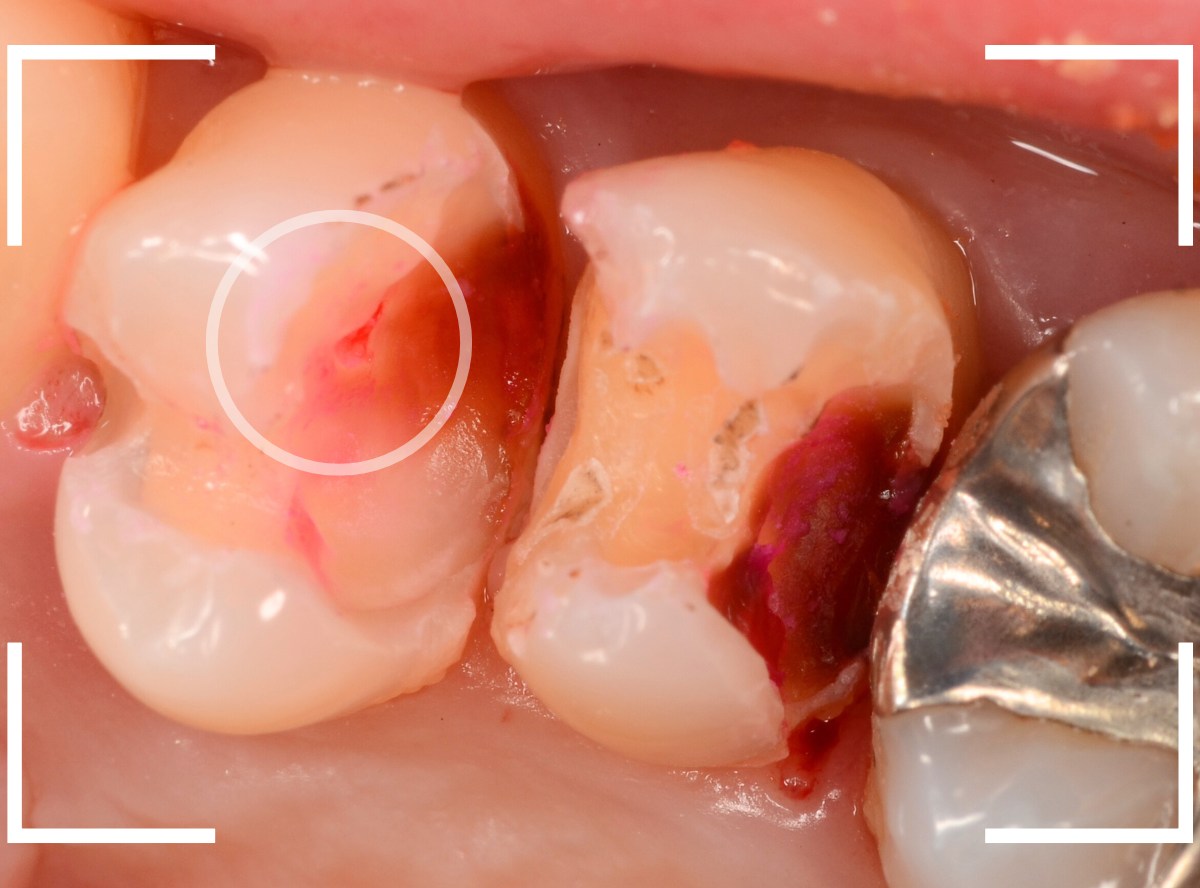

Case.23 歯のすきまから両側が大きな虫歯

「下の奥歯が痛む」という訴えで来院された患者さんのケースです。

目視でも、手前の奥歯がかけていて、中で虫歯が広がってるであろうことは予想できます。

ピンセットで歯を叩いてみても、手前の奥歯が痛むようです。

レントゲン写真で確認します。

青い線が神経、赤い線が虫歯の範囲です。

奥歯の方がより深い虫歯に見えますが、再度打診で確認したところ、やはり手前の奥歯が痛むそうです。

状況から、まず手前の奥歯から治療となりました。

麻酔をして、手前の奥歯のレジンを慎重に外します。

前に虫歯の治療をした時点で、神経スレスレの状態でしたので、削りすぎないように慎重にレジンを外さなければいけません。

レジンを外して、う蝕検知液で確認します。

レジンの中で虫歯が進行していたのがわかります。

慎重に全ての虫歯を除去しました。

何とか、神経が露出せずに済んでいます。

お薬をつめて、セメントで蓋をして経過観察します。

後日、状況を確認したところ、虫歯処置した後も、手前の奥歯が痛むとの事でした。

「我慢できないほどでもない」との事でしたので、引き続き経過観察しつつ、奥歯の治療を治療する事になりました。

奥歯は、レントゲンで見た通り、少し歯を削るとすぐに虫歯の穴が出てきました。

こちらは、ある程度虫歯を取ったところで染め出してみると真っ赤です。

ですが、何とか神経に達する前に、全ての虫歯を除去できました。

神経の治療が必要かと思っていたので、その点は幸運でした。

奥歯もお薬をつめて、セメントで蓋をして経過観察です。

何とか神経を取らずに済ませたいですが、どうなる事か・・・。